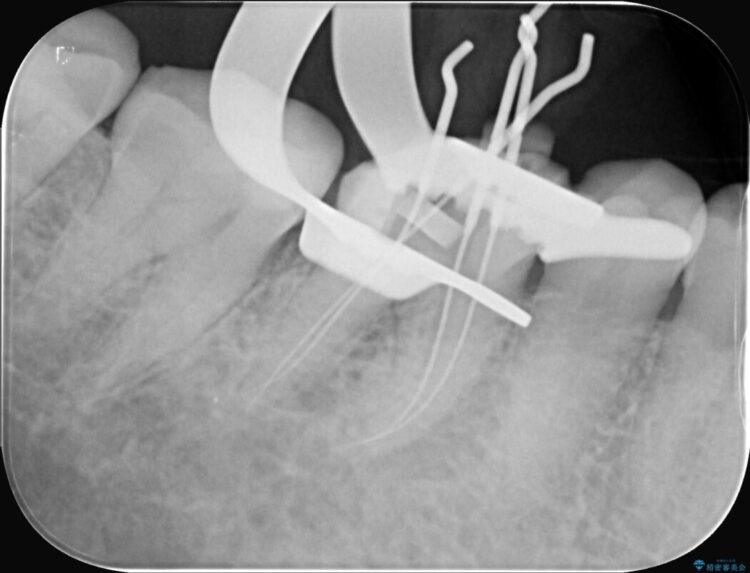

精密検査の結果、根の先に大きな病変が認められますが、根管内が狭窄し湾曲しているため、非常に難易度の高いケースです。

通常の治療器具では奥まで届かず、そのままでは再発や抜歯になるリスクが高いため、マイクロスコープを使用して根の奥まで精密に清掃・殺菌し、歯を残すための治療計画を立てました。

治療では、マイクロスコープで根の中を大きく拡大し、非常に細くなっていた神経の通り道を慎重に見つけ出しました。

次に、根のカーブに沿ってしなやかに曲がるニッケルチタンファイルを使い、根の先まで徹底的に洗浄・殺菌を行いました。汚れを完全に取り除いた後、隙間なくお薬を詰めて密閉しています。